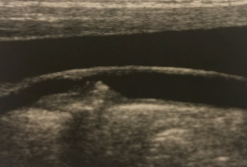

What kind of plaque is seen here?

Fibrous/Soft plaque